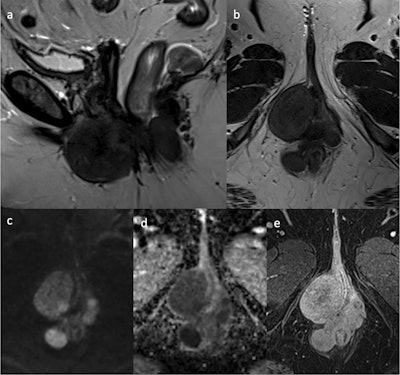

A 48-year-old woman who had already undergone a hysterectomy for multiple leiomyomas, presented with palpable masses at the level of the left labia minora and vagina. MRI shows multiple oval and round, well-defined masses at the level of the vulva, vagina, perianal, and perirectal. These lesions show hypointense signal intensity on sagittal (a) and axial (b) T2WI, with diffusion restriction on high b-value diffusion-weighted imaging (c) and ADC map (d), and homogeneous late enhancement in axial post-contrast fat-saturated T1WI (e). The final histologic diagnosis was extrauterine leiomyomas.